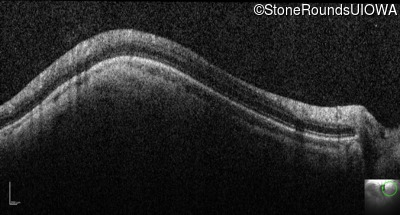

Optical Coherence Tomography - Right - 20/100

Exemplar